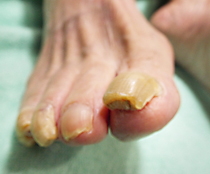

巻き爪、タコ、魚の目等があると症例に示すように、様々な症状を呈します。

早いうちに処置をして快適な生活を心がけましょう。